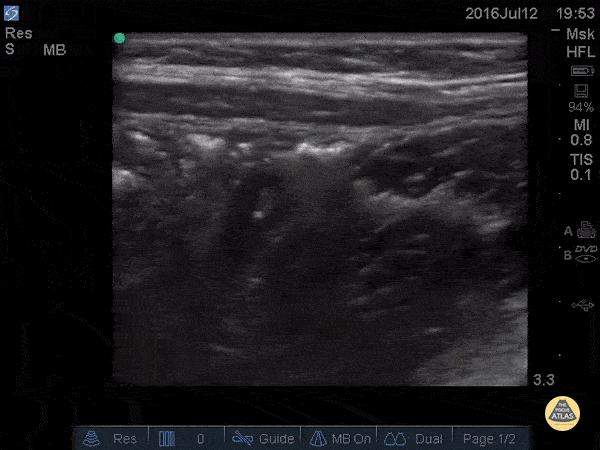

Peds-Gastrointestinal - Normal Appendix - Cross Section

14 y/o M with nausea vomiting and and RLQ pain. POCUS visualized a normal appendix is seen. A normal appendix is identified by a blind-ending tubular structure that is <6mm diameter measured from outer wall to outer wall (although 6mm-7mm has also been described). This patient’s appendix was measure to be 5.4mm (see still image). Dr. Sathya Subramaniam - Children’s Hospital of Philadelphia